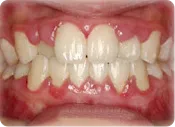

歯肉炎

歯肉にのみ炎症が生じたもので、歯根膜や骨(歯槽骨)までは破壊されていないもの。

歯肉は暗赤色で丸みを帯びて腫れ、歯磨きの時や固いものを食べた時に出血しやすくなります。

正しいブラッシングと歯石除去で良くなります。